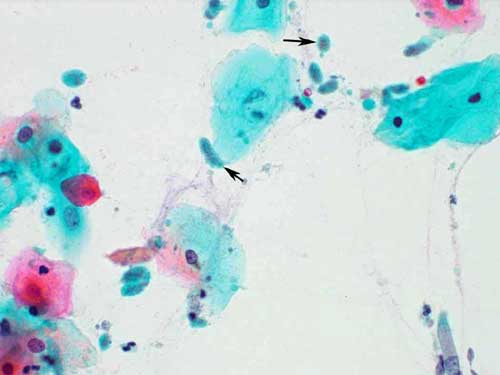

trich2